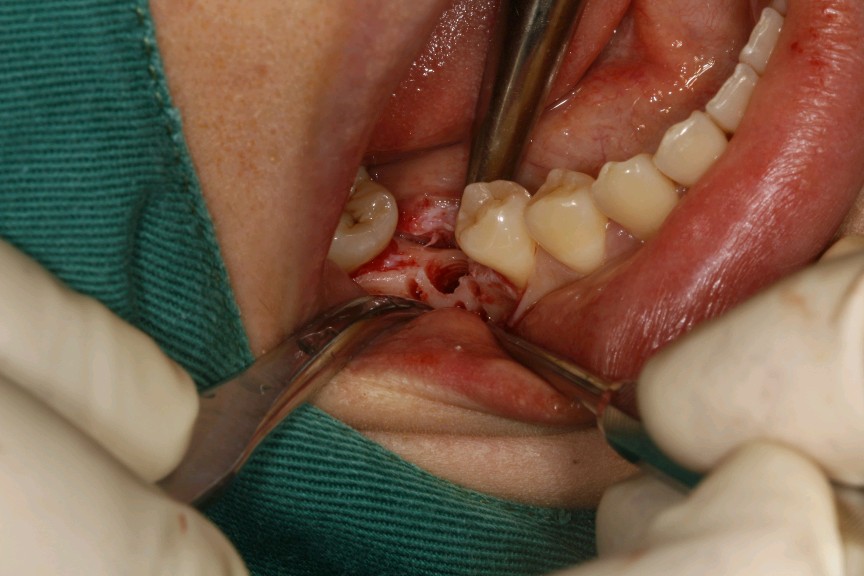

患者女,二十七岁,46牙体缺失近一年,牙槽崎吸收较多,粘膜无红肿、对合牙轻度伸长,邻牙轻微松动,龈周﹣。 x 示牙槽骨密度正常。告知患者治疗方案,患者选择种植修复。抽静脉血20ml,制作 CGF ,植Nobel Pcc 种植体4.3*10mm,上覆盖帽,颊侧骨缺损区植入 bio - oss 骨粉0.25g及 CGF ,盖 bio - Gide 膜及 CGF 膜,严密缝合。直至今日戴牙,咬合适宜,患者满意。